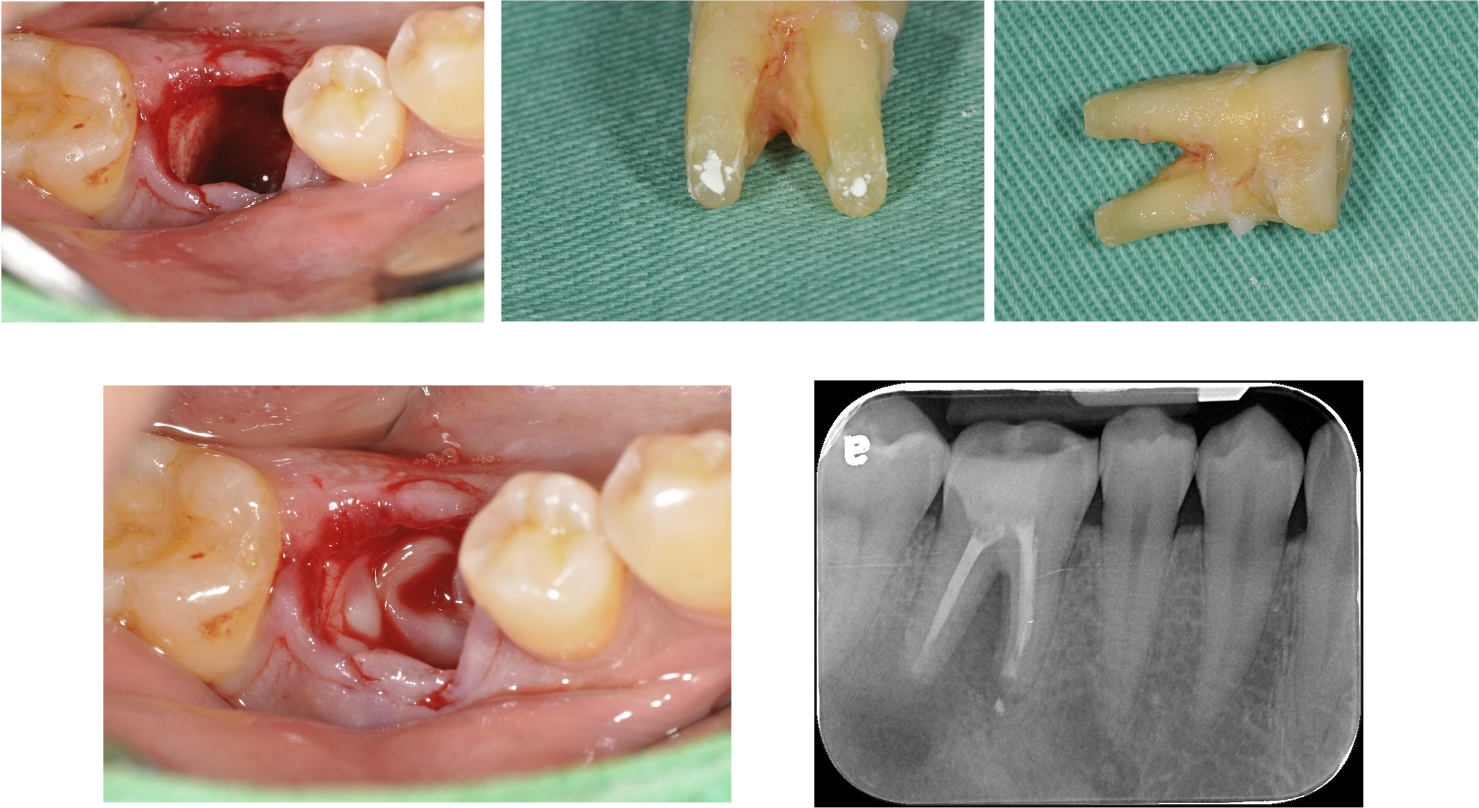

牙齒拔出,刮除根尖病變

6個月後,根大病變癒合

巨大的根尖病變,有時需要牙髓手術輔助,才能順利拯救牙齒,而現今陶瓷冠塊體修整牙齒較少,可有效保護牙齒結構。